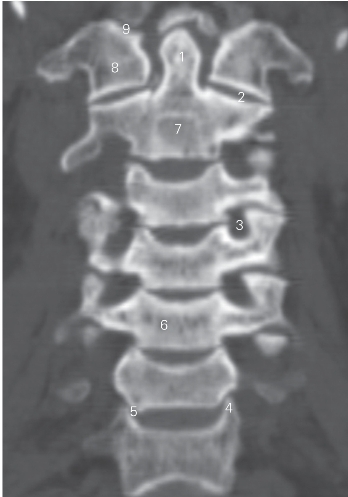

图1-3 经齿突的冠状断层CT图像(骨窗)

1 齿突 odontoid process 2 寰枢关节 atlanto-axial joint

3 横突孔 transverse foramen 4 椎体钩 uncus of vertebral body

5 钩椎关节 uncovertebral joint 6 第5颈椎体 5th cervical vertebral body

7 枢椎 axis 8 寰椎 atlas

9 寰枕关节 atlantooccipital joint